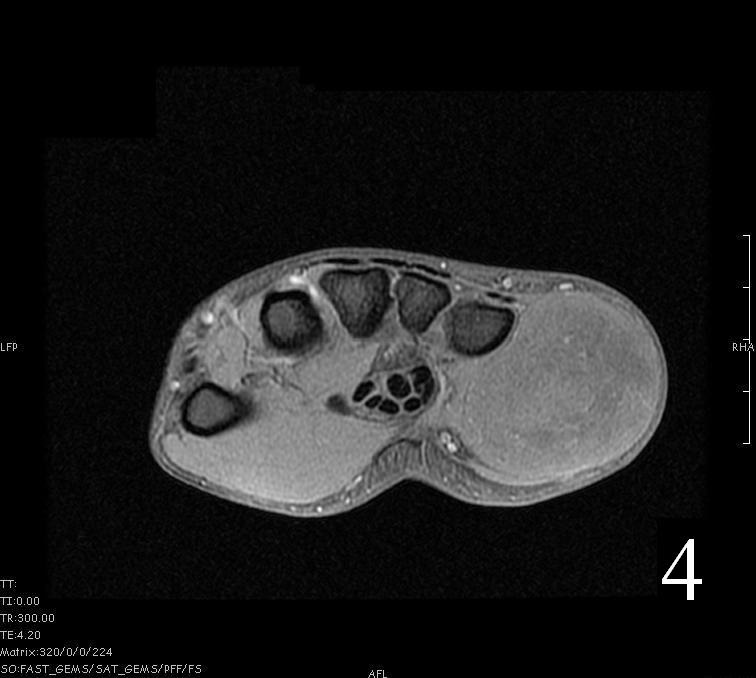

MRI

- Heterogeneous mass (does not follow signal of skeletal muscle)

- Isointense to skeletal muscle on T1 (Fig. 4, Fig. 5, Fig. 7, Fig. 8)

- Hyperintense signal on T2, sometimes low to intermediate signal on T2 if there is extensive fibrous tissue within the tumor (Fig. 6, Fig. 9).

- Prominent vascularity

- Deep enhancement with gadolinium

- Possible extensive hypercellular fibrous tissue and hemosiderin seen on T2

Fig. 4-9: MRI of a rhabdomyosarcoma of the hand. The MRI is nonspecific and shows a heterogeneous mass particularly on postgadolinium images T1 W images (Fig. 8) and T2 W images (Fig. 9).